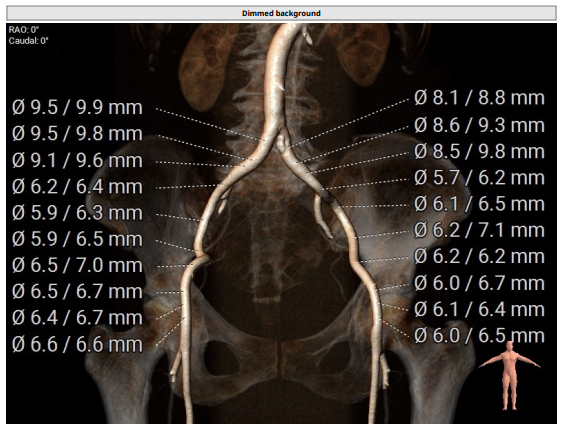

CT评估

1.瓣环及左室流出道。

2.主动脉瓣根部(左右瓣叶长度均超过冠脉高度)。

3.主动脉弓分析及瓣叶长度(最短弓距小于70mm)。

4.外周血管入路